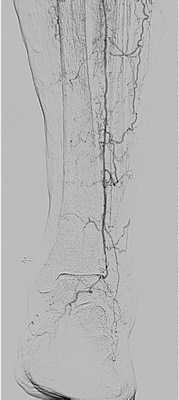

Ангиография

Для решения вопроса хирургической тактике необходима информация о проходимости артерий пораженной конечности. Выбор методики восстановления кровообращения зависит от состояния путей притока к пораженной конечности и сосудистого русла ниже места закупорки. Кроме того, при ангиографии можно отличить эмболию от тромбоза на фоне атеросклеротических сужений. Во время ангиографического исследования можно предпринять эндоваскулярное лечение в объеме тромбэктомии и ангиопластики пораженных сегментов или провести локальную тромболитическую терапию.

Ангиография проводится на операционном столе для уточнения воспринимающего сосудистого русла и позволяет определить характер хирургического вмешательства